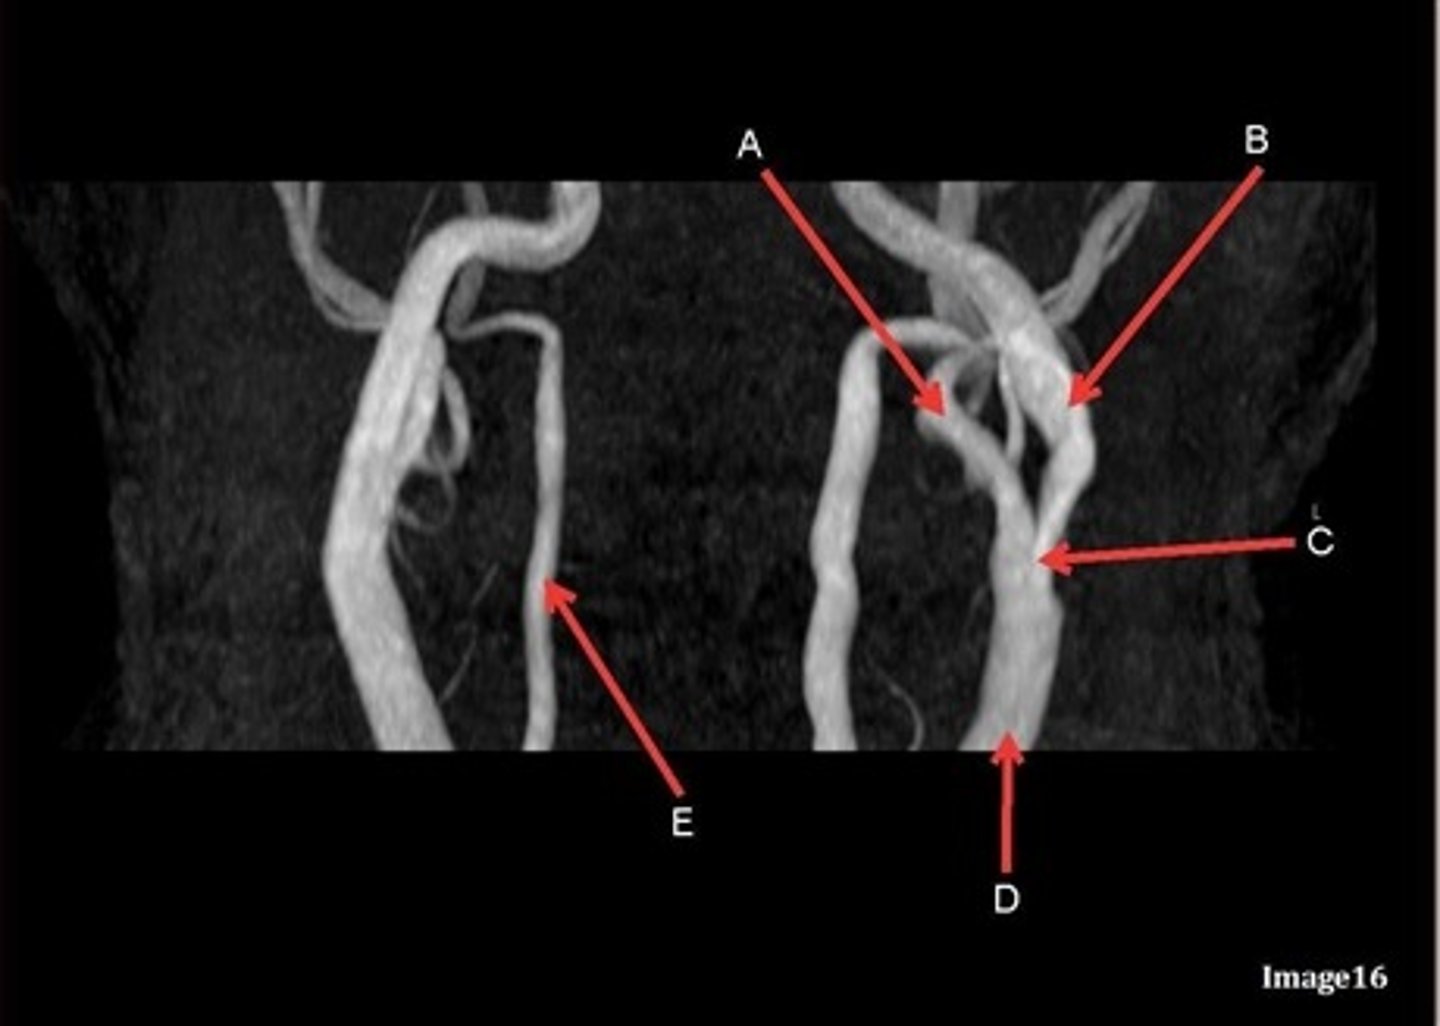

A, where does it supply blood to?

external carotid artery

face

B, where does it supply blood to?

internal carotid artery, anterior brain

C

Common carotid bifurcation

D

common carotid artery

E, where does it supply blood to?

vertebral artery, posterior brain

what kind of image is this?

MRA extracranial circulation